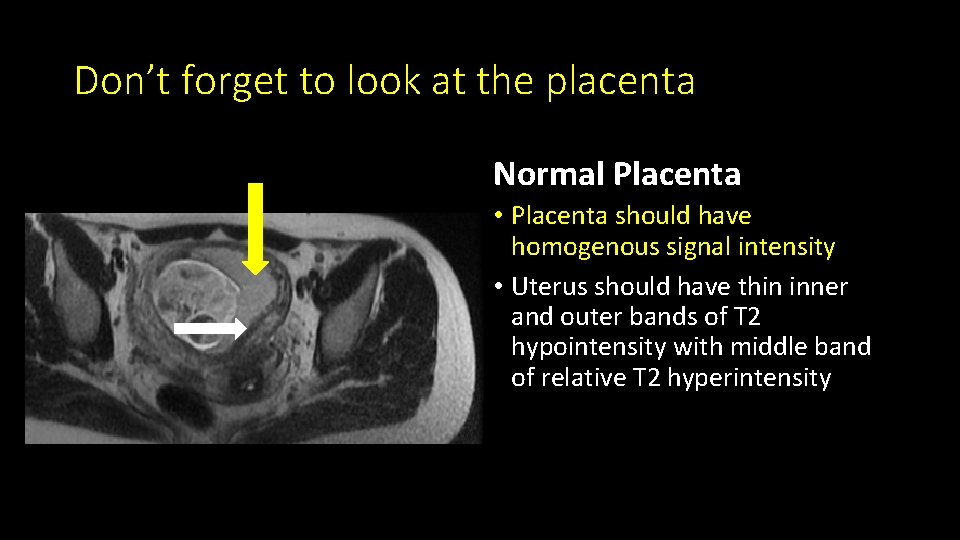

Don’t forget to look at the placenta Normal Placenta • Placenta should have homogenous signal intensity • Uterus should have thin inner and outer bands of T 2 hypointensity with middle band of relative T 2 hyperintensity